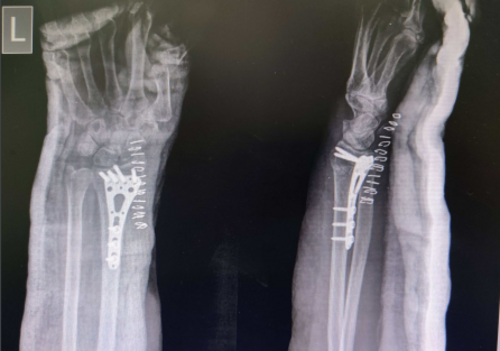

Successful ORIF Treatment for Elderly Distal Radius Fracture: Dr. Rahul Jagtap

Dr. Rahul Jagtap, an orthopedic surgeon based in Navi Mumbai, successfully treated an elderly patient suffering from a distal radius fracture and oste...